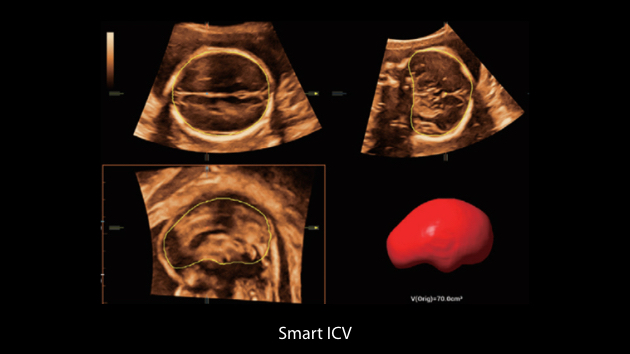

Gambar Klinis